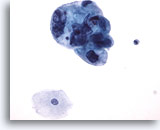

Figure 47

Bladder urine, low grade carcinoma

A loose cluster of cells from low grade urothelial carcinoma can be compared to reactive urothelial cells. 20x

Bladder urine, low grade carcinoma

A loose cluster of cells from low grade urothelial carcinoma can be compared to reactive urothelial cells. 20x

Figure 47

Bladder urine, low grade carcinoma

A loose cluster of cells from low grade urothelial carcinoma can be compared to reactive urothelial cells. 20x

Bladder urine, low grade carcinoma

A loose cluster of cells from low grade urothelial carcinoma can be compared to reactive urothelial cells. 20x